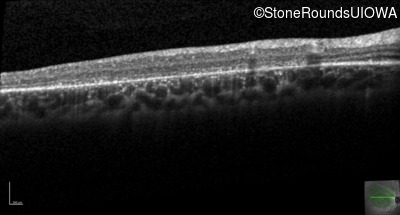

AR Stargardt Disease (IIA)

AR Stargardt Disease (IIA)

| Age at visit: 12 years |

| Age at visit: 13 years |

| Age at visit: 15 years |